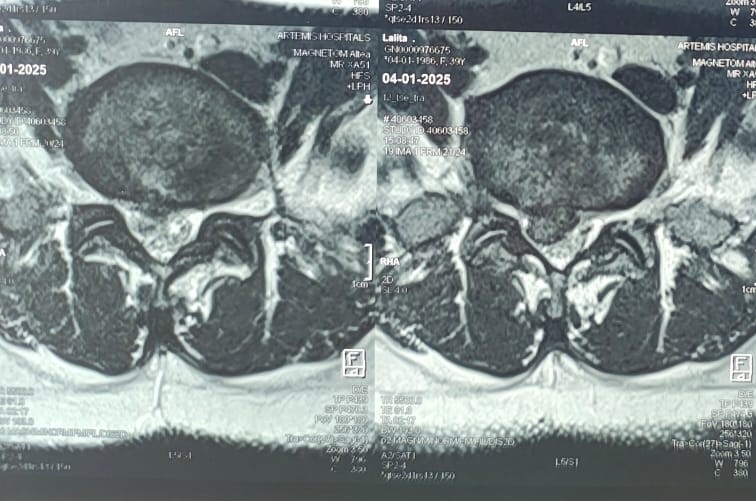

Endoscopic discectomy is a minimally invasive spine surgery procedure used to treat disc herniation in the lumbar spine. The procedure involves accessing the herniated disc through a small incision in the back using an endoscope, a thin tube with a camera and surgical instruments attached. By visualizing the herniated disc on a monitor, the surgeon can precisely remove the herniated portion of the disc, relieving pressure on the spinal nerves and alleviating symptoms such as pain, numbness, and weakness.

– Lumbar disc herniation causing radicular symptoms (sciatica)

– Persistent or severe back and leg pain that does not respond to conservative treatments such as medication or physical therapy

– Disc herniation compressing spinal nerves, leading to neurological symptoms such as weakness, numbness, or tingling in the legs